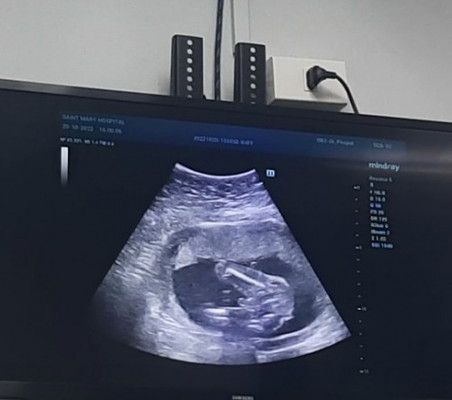

สาวได้รูปแบบเดียวกันเลยค่ะแต่อันนี้มืดมากแต่หมอบอกว่าน้องมีกระจู๋โผล่แล้วเห็นลูกอัณฑะด้วยแต่ตัวแม่ไม่เห็นเพราะมันมืดมากคลอดเดือนมีนาคมเหมือนกันขอให้แข็งแรงนะคะคุณแม่

กำหนดคลอด 19 มีนา 66 ซาวเห็นเพศแล้ว หมอว่าเพศชาย แต่ยังไม่คอนเฟิร์มเพราะสายรกบัง รอซาวอีกทีหมอนัดรอบหน้าค่ะ

กำหนดคลอด 21มีนาคม66 ค่ะ ไปซาวด์ครั้งล่าสุด คุณหมอเลื่อน 17มี.ค. ซาวด์เห็นเพศตั้งแต่ตอน12w ค่ะ เพศชาย

กำหนดคลอด 22 มีนา ได้ ผู้ชาย ค่ะ น้องนอนให้เห็นตั้งแต่เดือนที่ 4 เลย 😂 แม่ไม่ต้องลุ้นกันเลยยจ้าา